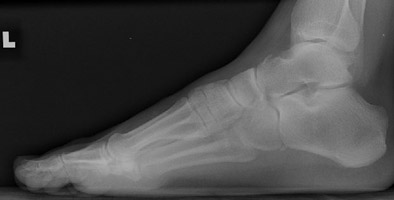

A | Lateral radiograph of the foot. This demonstrates a small cortical fragment just superior to the talus due to avulsion injury. |

In addition to fractures described by the term aviator's astragalus, other talar injuries are usually the result of ligamentous avulsion by forced dorsiflexion of the foot. The talus may be injured at the head, neck, body, or posterior process. Neck fractures are the most common. The talus is the second most fractured bone of the foot.